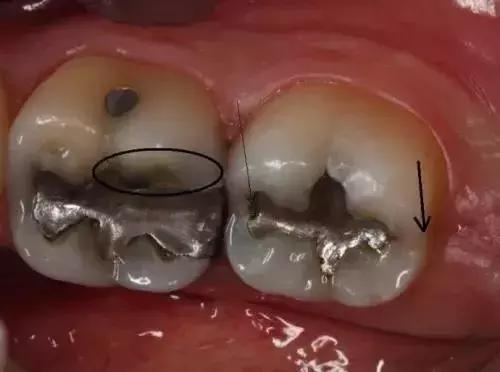

牙隐裂—*毒冰**会使服用者感到焦虑、亢奋或紧张,从而导致磨牙。你能看到他们的牙齿上有明显的磨耗痕迹。有时候就算是吃一些很软的食物(如土豆泥),也会使服用者的牙齿出现隐裂。

龋齿—*毒冰**成瘾者会因为口干反应而渴望吃含糖量高的食物和饮品。这样,口腔内靠糖类为生的细菌会大量繁殖,并分泌酸性物质,使牙齿损坏更严重。*毒冰**服用者的龋齿通常会从牙龈边缘发展到整个牙齿,前牙首当其冲。

*毒冰**牙的第一阶段

出现龋齿,口臭,牙龈红肿

*毒冰**牙的第二阶段

嘴唇上出现伤口,牙龈开始退缩,龋齿呈严重趋势

*毒冰**牙的第三阶段

龋齿发展到牙龈边缘以下,牙齿出现缺失,嘴唇的伤口越发明显